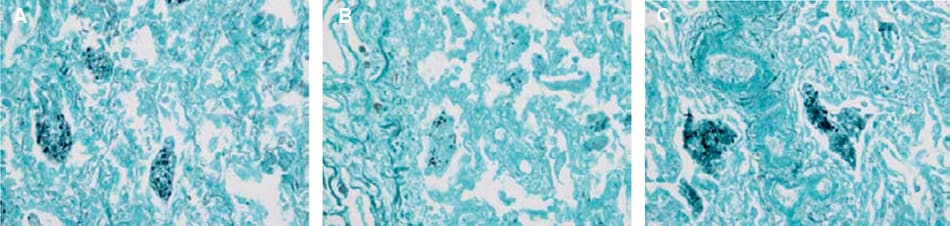

The GMS staining yielded high-quality results with no background staining when Elix® pure water was used to prepare reagents (Figure 1A). Distilled water (B) lightened the staining of the organisms but did not contribute to background staining. Deionized water (C) appeared to intensify background staining as well as staining of P. jirovecii. Pure water from a Milli-Q® IX water purification system can therefore substitute for distilled or deionized water called for in GMS staining procedures.

Figure 1.Photomicrographs of lung tissue infected with Pneumocystis jirovecii and stained with GMS stain. Methenamine silver nitrate solutions were prepared with (A) Elix® pure water, (B) distilled water, and (C) deionized water. Pictures courtesy of E. Macrea and W. Lange.